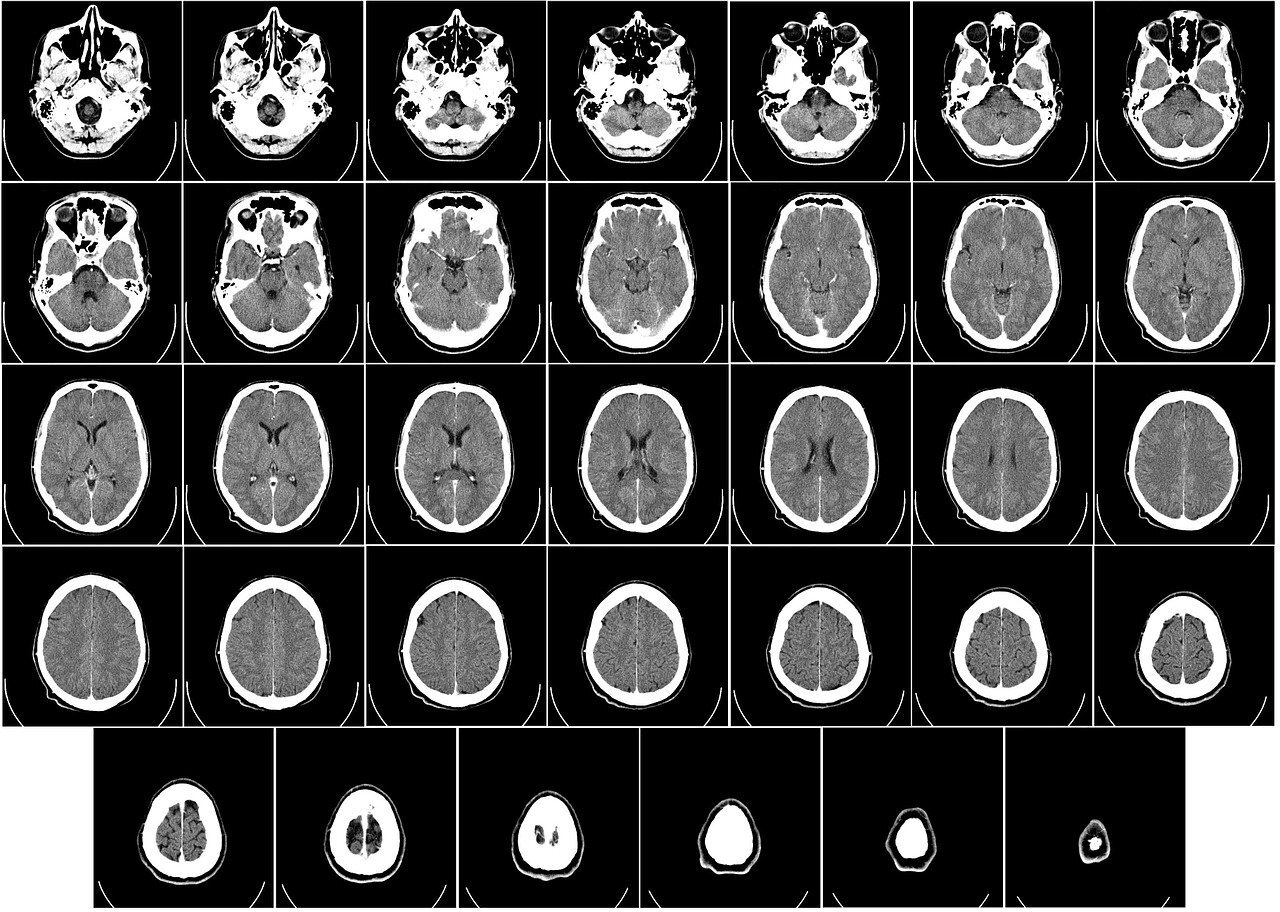

뇌졸중은 뇌경색과 뇌출혈 두 가지로 분류됩니다. 혈관이 막혀서 뇌의 일부가 손상되는 뇌경색과 뇌혈관이 터져서 뇌 안에 피가 고여 그 부분이 손상된 뇌출혈이 있습니다.

뇌경색이 뇌출혈보다 약 85% 정도 많이 발생합니다. 뇌졸중은 국내 사망률이 아주 높은 질환으로 목숨은 건졌다 하더라고 뇌 손상에 의한 신체장애로 인한 후유증이 상당합니다.